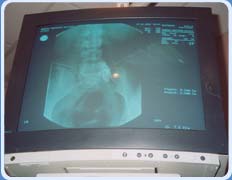

• Fluoroscopia.

• Intensificador de imágenes digital

6) Bloqueos: epidural, espinal o subaracnoideo, ganglionar, plexo y simpático, los bloqueos se realizan con monitorización continua en quirófano equipado eficientemente, con estudios laboratoriales e intensificador de imagen.